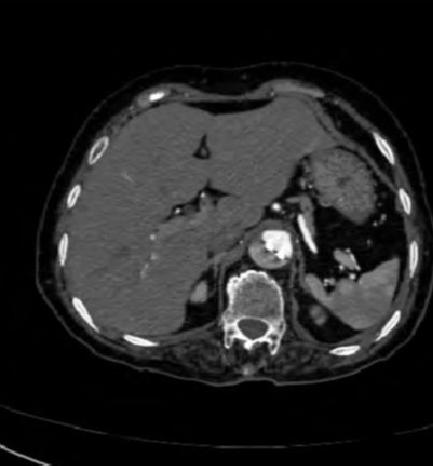

病例7

你看,我家的CT这么模糊,平扫怎么看主动脉夹层?

图18

不着急!仔细看,血管里面的“血液”居然钙化了!这叫血管钙化内移,要警惕主动脉夹层!有研究发现,血管钙化内移诊断动脉夹层的特异性高达90%。

图19

赶紧做个增强CT!主动脉裂开了!

图20